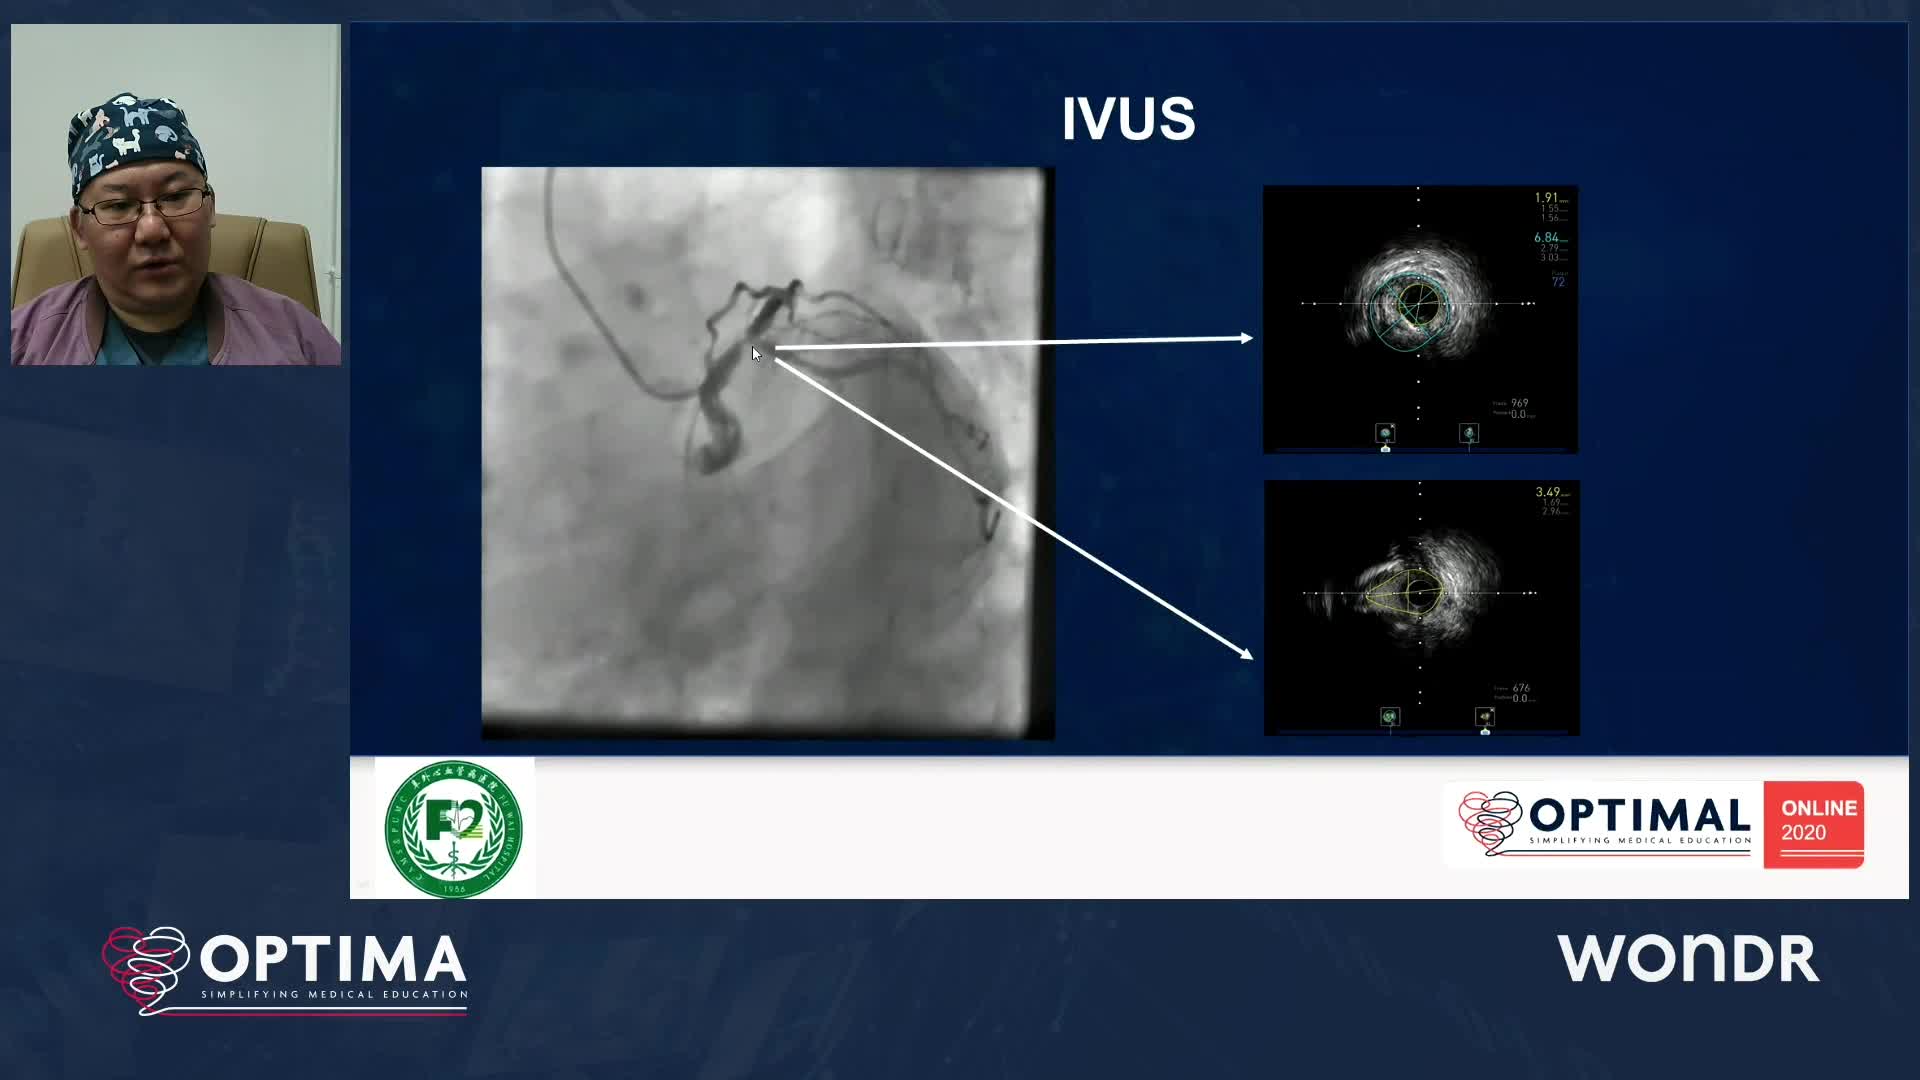

The integrated use of physiology and imaging is transforming the treatment of complex bifurcation disease. We explore...